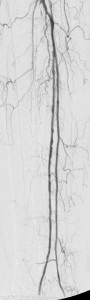

After instituting strategies to minimize contrast-induced nephropathy, I employed atherectomy of the distal LSFA and popliteal stenoses and angioplasty of the multifocal stenoses of her anterior tibial artery down to the dorsalis pedis artery to restore reasonable flow to her foot that helped the ulcer heal.

Images in the top panel illustrate her disease before the interventions, those in the middle panel illustrate some intraprocedural steps (balloon angioplasty), while those in the bottom panel illustrate improved blood flow to the foot following treatment.